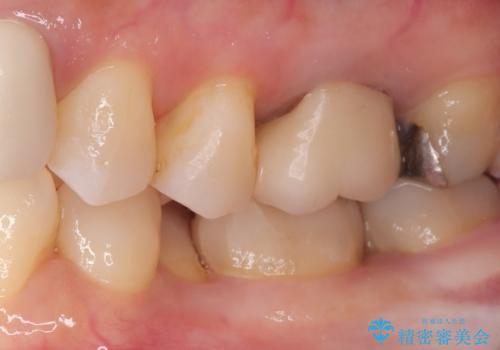

- 主訴:口を開けると所々入っている銀の詰め物が目立つので白い物にやり替えたい。

下顎大臼歯部に入っている保険適用のメタルインレーを、適合性と審美性の良いセラミックインレーでのやり替えとなりました。

メタルインレーを除去した際、古い裏層材やカリエスは除去し新たにCR裏層しています。

セラミックインレーセット時はラバーダム防湿を行っています。